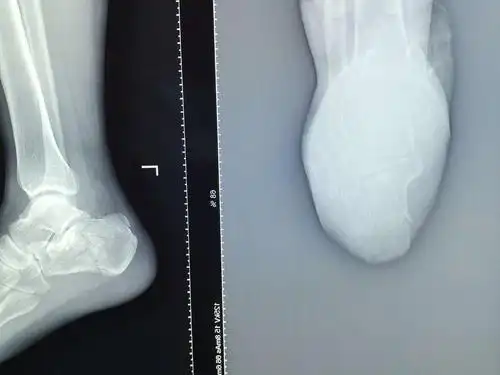

跟骨骨折术后请赐教

左侧跟骨骨折

一例跟骨骨折

跟骨骨折闭合复位1例

跟骨骨折微创是趋势

左脚跟骨,骨折需要手术吗,懂行的帮我看哈

左跟骨骨折